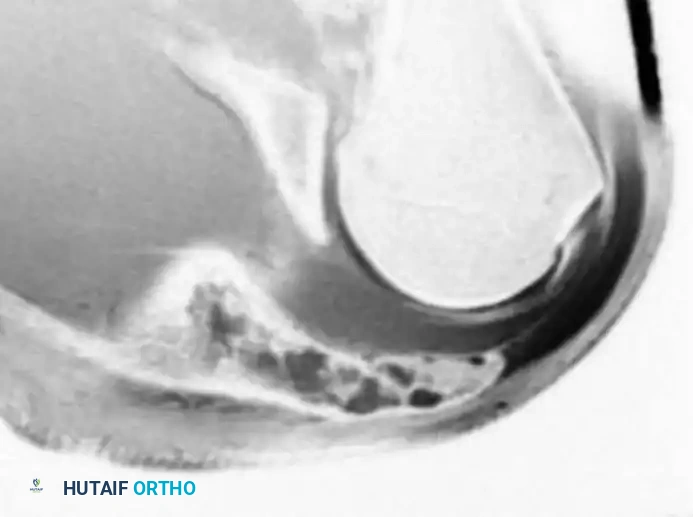

Intraoperative Imaging and Margin Assessment

Continuous intraoperative assessment using fluoroscopy and frozen section pathology is mandatory. The following images demonstrate various stages of complex upper extremity resections, allograft preparations, and prosthetic implantations across the humerus and elbow joint.

Distal Humerus and Elbow Reconstruction

When tumors involve the distal humerus, resection often requires sacrifice of the collateral ligaments and the articular surface of the elbow. Reconstruction is typically achieved using a linked, semi-constrained total elbow arthroplasty designed for oncologic defects.